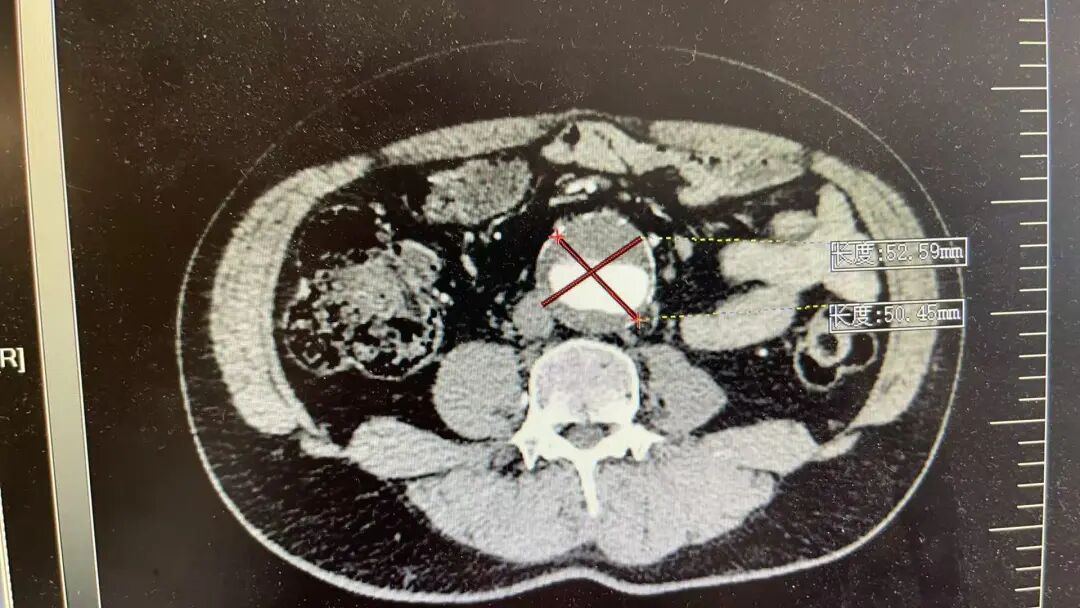

这两位患者情况差不多,他们平日里身体并无明显不适,在一次常规体检中,腹部超声检查结果显示,腹主动脉存在瘤样扩张,进一步检查确诊为腹主动脉瘤,并同时累及双侧髂总动脉,形成髂动脉瘤。

瘤子长在什么位置?腹主动脉是人体腹部最粗大的一根动脉,大致位于肚脐的后面、脊柱的前面,负责将心脏泵出的血液输送到下半身。到了肚脐下方约三四指的位置,它分叉成左右两条髂总动脉,继续向双腿延伸。患者情况比较特殊,动脉瘤不仅累及了腹主动脉主干,还向下延伸到了分叉区域。

当动脉壁因为老化、高血压、动脉硬化等原因变得薄弱,在持续的血流冲击下,局部像吹气球一样膨胀起来,就形成了腹主动脉瘤。它平时可能毫无症状,但一旦破裂,患者会在极短时间内因大量失血而休克,死亡率极高。幸运的是,患者动脉瘤还没有破裂,正因为发现得早,医生才有充足的时间进行术前评估,选择最稳妥的手术方案。